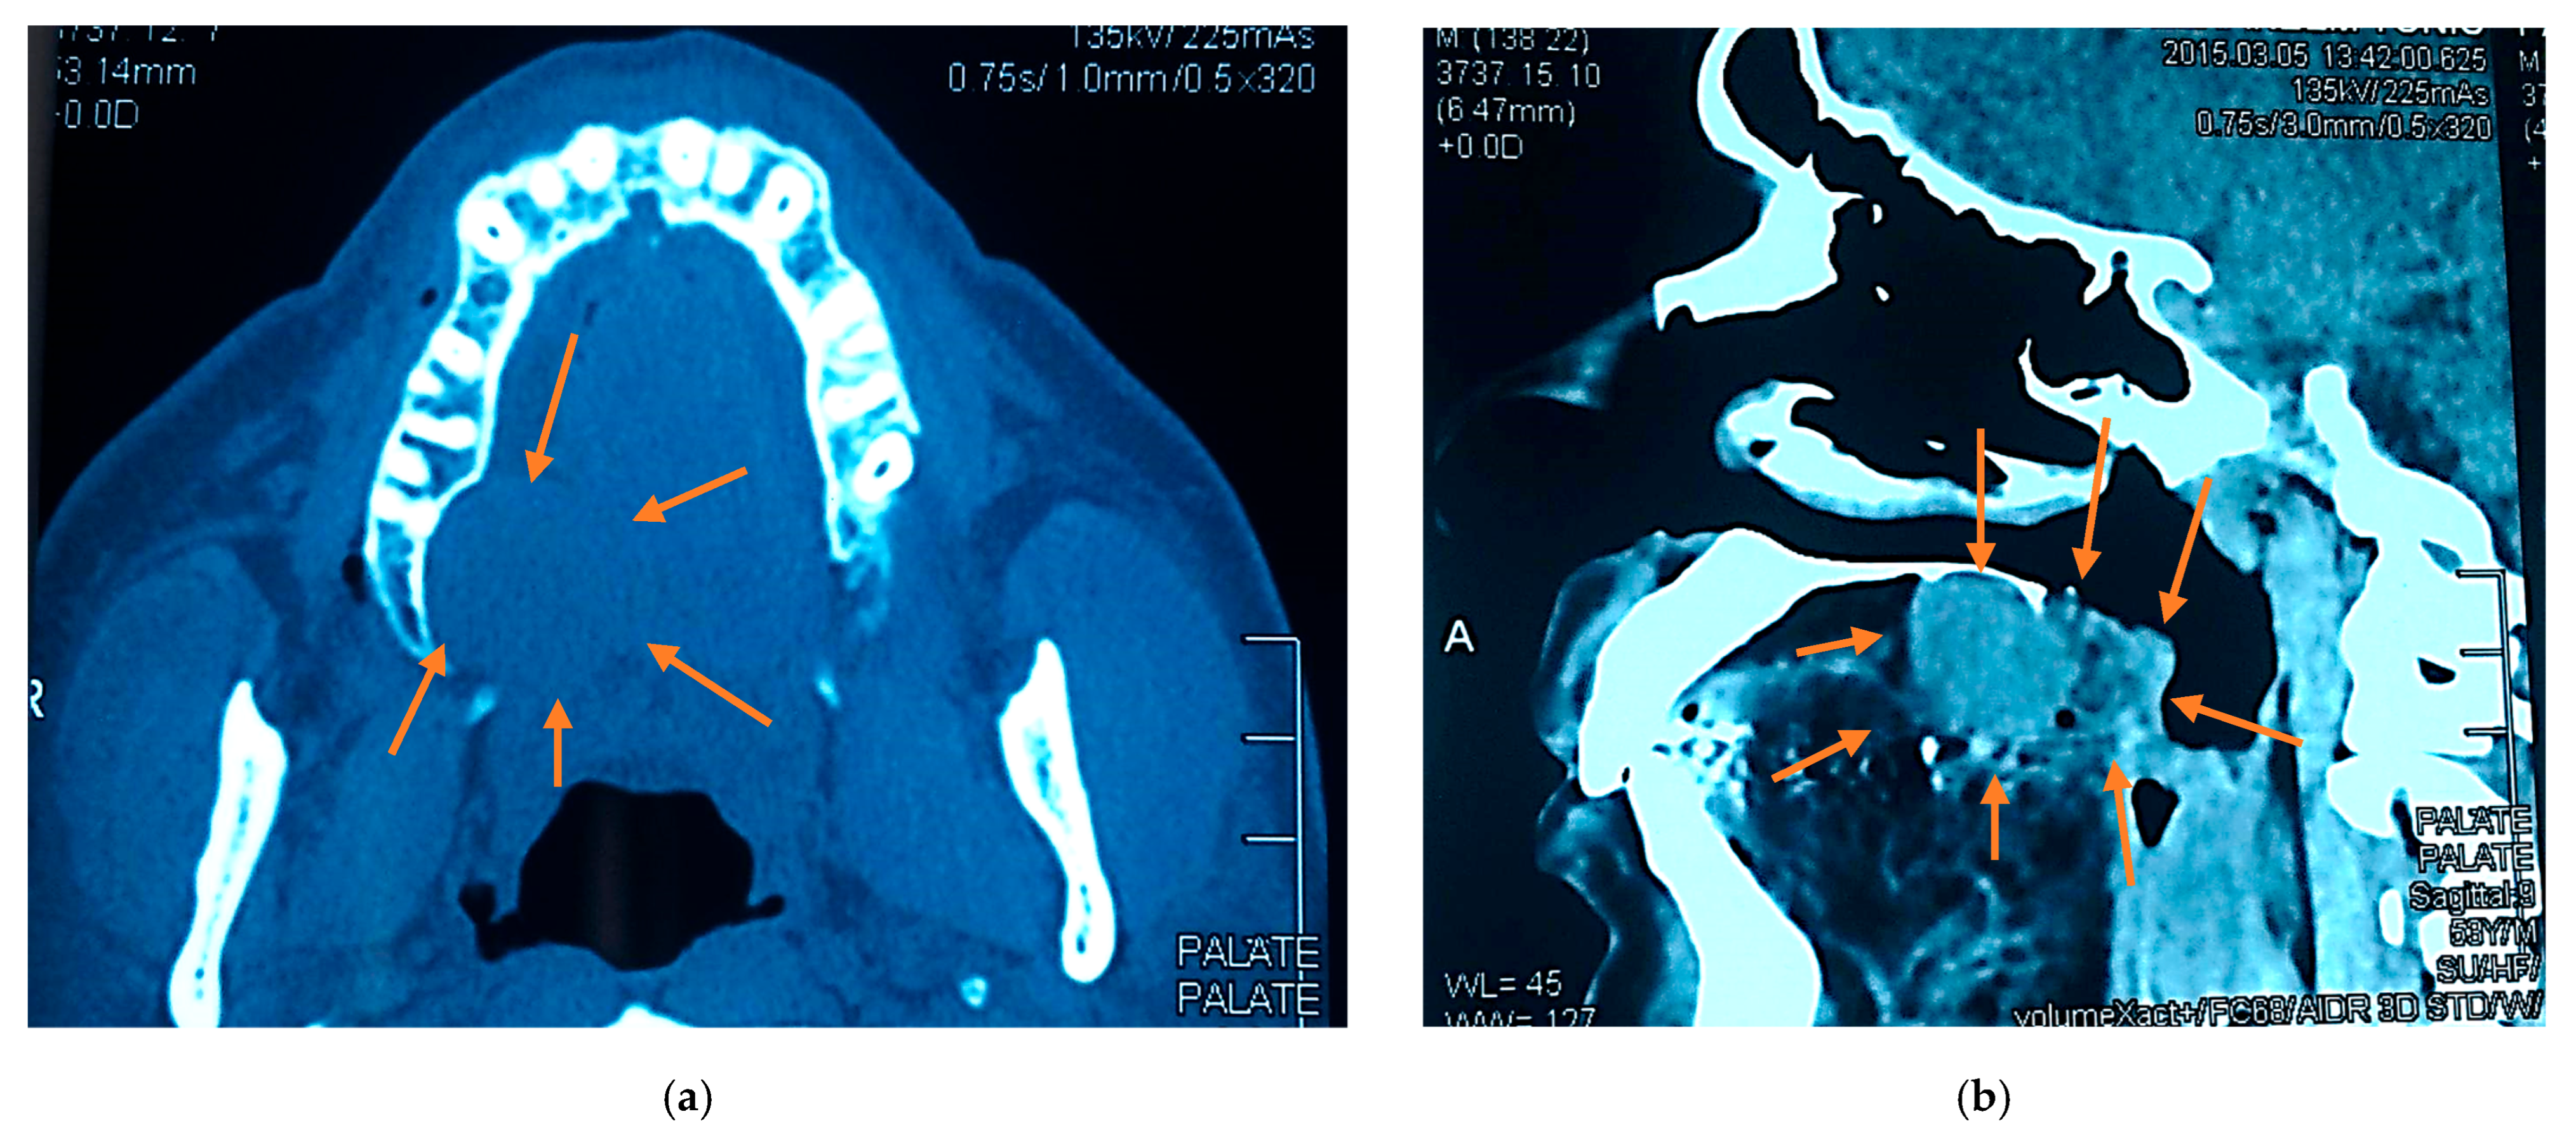

2.3. Radiographic Examination